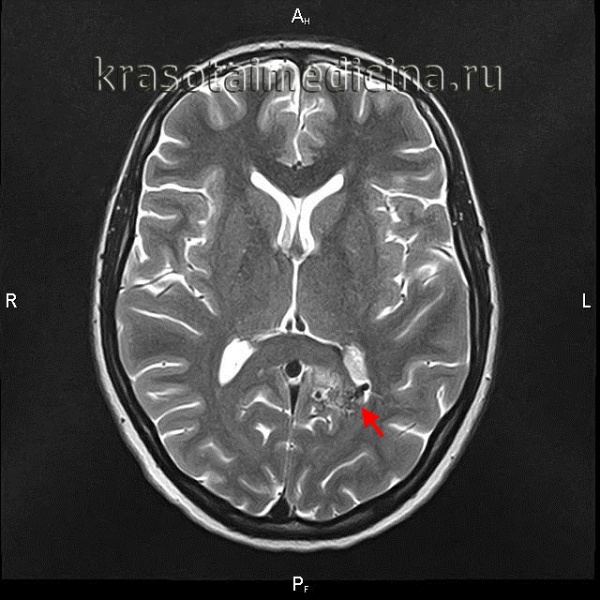

Поводом для обращения к неврологу до разрыва АВМ могут быть упорные головные боли, впервые возникший эпиприступ, появление очаговой симптоматики. Пациенту проводится плановое обследование, включающее ЭЭГ, Эхо-ЭГ и РЭГ. При разрыве АВМ диагностика осуществляется в экстренном порядке. Наиболее информативны в диагностике сосудистых мальформаций томографические методы. Компьютерная томография и магнитно-резонансная томография могут быть использованы как для визуализации тканей мозга, так и для исследования сосудов. В случае разрыва АВМ МРТ головного мозга более информативно, чем КТ. Она дает возможность выявить локализацию и размер кровоизлияния, отдифференцировать его от других объемных интракраниальных образований (хронической гематомы, опухоли, абсцесса головного мозга, церебральной кисты).

При торпидном течении АВМ МРТ и КТ головного мозга могут оставаться в норме. Обнаружить сосудистую мальформацию в таких случаях позволяет лишь церебральная ангиография и ее современные аналоги — КТ сосудов и МР-ангиография. Исследования церебральных сосудов проводятся с использованием контрастных веществ. Диагностика осуществляется нейрохирургом, который также оценивает операционный риск и целесообразность хирургического лечения АВМ. При этом следует учитывать, что при разрыве, в связи с компрессией сосудов в условиях гематомы и отека мозга, томографический размер АВМ может быть существенно меньше реального.

- МРТ спинного мозга. Позволяет визуализировать артериовенозную мальформацию, диагностировать спинальное кровоизлияние, определить его объём и расположение.